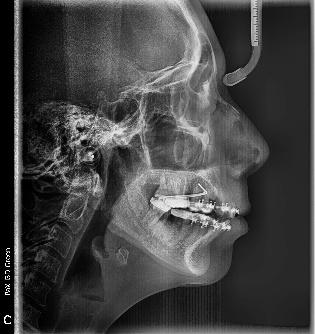

Estudios radiográficos de inicio

En la radiografía lateral de cráneo (Figura 4) se ve la aparatología con la que llegó la paciente, el perfil es convexo, hiperdivergente y las vías aéreas permeables.

Figura 3. Oclusal superior e inferior. Figura 4. Radiografía lateral de cráneo de inicio.